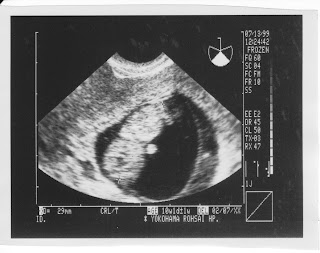

ママぶたのおなかん中~その8~

1999年7月13日

さて、こいつも向こう向きな感じ。

まだちびっちゃいからか、羊水もたっぷりで空間も余裕がある感じ。

包まれて眠ってるというよりは、泳いでる感じ。

親の体温で、水の中で。

息をしなくても苦しくなく眠れるってのは…

なんか、とっても気持ちよさそうだ♪

きっと、こんなに気持ち良い睡眠はこれから味わえないかも知れない。